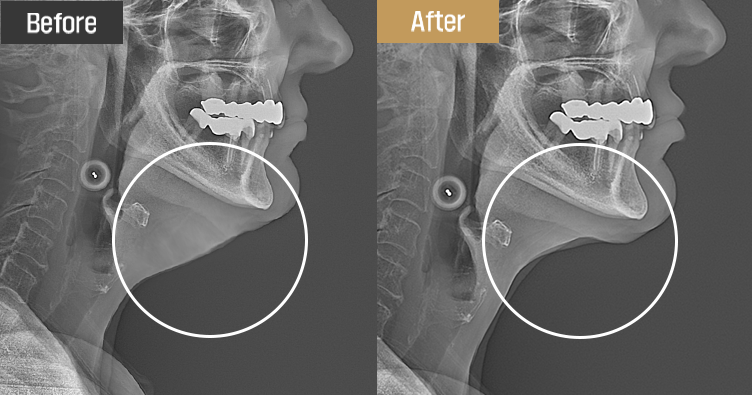

手術直後、レントゲンで効果をすぐに確認できます。